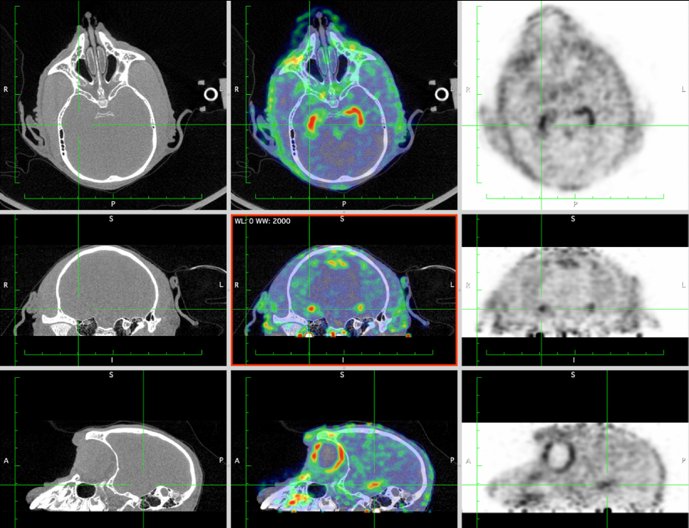

CASE 3: NHP brain PET/CT dynamic FDG imaging

• Courtesy of: CERMEP, Lyon, France

Research objective: Investigation of FDG uptake in NHP brain

Animal model: NHP, ~ 3 kg

Acquisition protocol: PET imaging: 60 min acquisition, injection right after acquisition starts. CT imaging: 80kV, 40s

Processing and reconstruction protocol: PET: 3D OSEM, 6x 10 min, 0.84 mm isotropic voxel size. CT: 0.15 mm isotropic voxel size

Biomarker or contrast agent: 18F-FDG, ~ 3 mCi